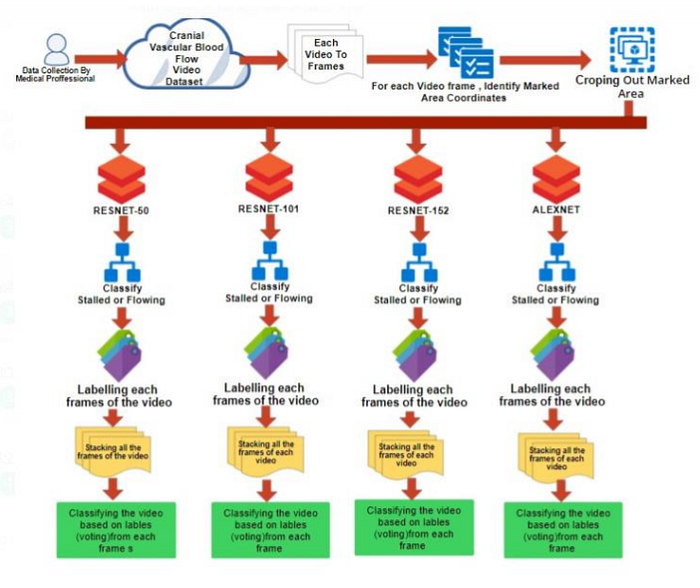

Flow Diagram

The steps that we have followed from collection of data, data processing and cleaning and our analysis.

- The dataset consisted of 4600 videos of cranial vessels classified as flowing or stalled

- After extracting the frames and manual filtering of the images, a dataset of 78675 images in total was created. If we observe the dataset in a scrupulous manner, we find out that the difference between the images as a whole is quite inconsequential. The difference between both the classes viz. blood flowing and stalled in the cranial vessel can be determined only by the region outlined in these images. So, unless and until we consider just the outlined region, the difference in both the classes seems irrelevant. Hence, extraction of the outlined region in a particular image becomes extremely important.

3. Furthermore, once the frames were extracted from the videos, these images were cropped to train the classifier. Regions of blood flow and stalled vessels were randomly cropped from the extracted frames.

4. This exercise was performed to train the classifier in a more efficient way by omitting the unnecessary parts and extracting the necessary data from the images.

5. The above images where then classified using four distinct architectures viz. Resnet50, Resnet101, Resnet152 and AlexNet. The logic that is used in the classification is that in case when blood is actually flowing through the vessel a luminescent spot is picked up by the algorithm whereas in case when the blood is not flowing or stalled a black spot can be observed. So when we are looking at images of a non Alzheimer individual the frequency of these bright luminescent spots would be higher as compared to the black spots and vice versa for an Alzheimer infected person. Whichever algorithm is able to best pick up this difference will give us the highest accuracy